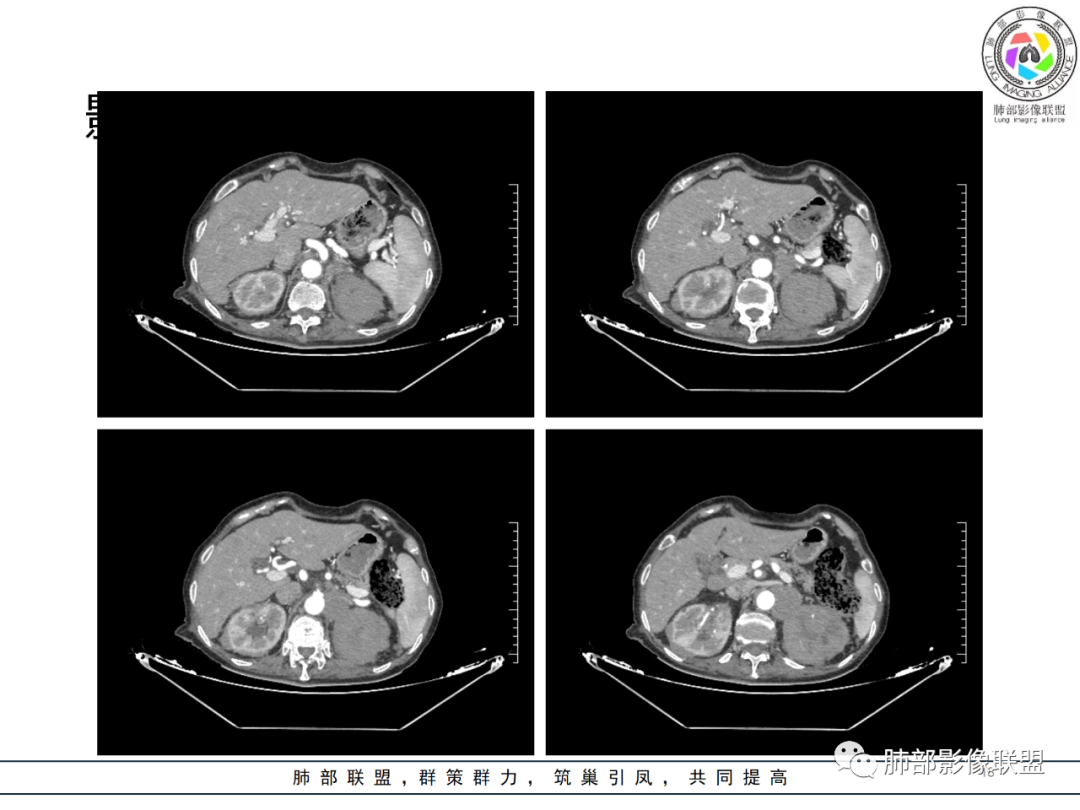

影像资料

老年女性 3个月前发热,双肺支气管血管束增粗改变。3个月后再次发热,影像见双肺广泛支气管血管束明显增粗,较前进展,并延续进入纵隔,另外增强见双肾周增多软组织密度,左肾明显且肾门处形成肿块样改变。综合考虑肿瘤性病变可能性大,1.小圆细胞肿瘤类病变,淋巴瘤?2 全身组织细胞类病变,如ECD,需要看看骨组织有无问题。3 左肾恶性肿瘤并淋巴道播散,如弥漫性尿路上皮癌。最后考虑 淋巴瘤>ECD>左肾恶性肿瘤并转移。

82岁女性,反复发热入院,查外周血白细胞升高,抗生素治疗可缓解,支持细菌感染性发热,结合肾脏肿瘤,考虑泌尿系感染发热;CT提示双肺多发毛玻璃影,右下肺多发大结节影,3月复查,双上肺毛玻璃影/混合毛玻璃影增多,部分呈点晕征,右下肺多发肿块,可见支气管穿行,双下肺中轴间质增厚,左肾占位,肺部病变考虑:1.淋巴瘤 2.肾癌肺转移

如果说两肺病变生就一张“大众脸”,但腹部异常影像却带给我们一些重要线索! 双肾病变变现为浸润性累及肾周、延及深静脉,而非典型膨胀性,低密度少血供,腹膜后肿大的淋巴结同样强化不明显,这些都符合典型的浸润性肾淋巴瘤的影像表现。注意患者肾上腺低密度结节影及脾脏多发结节影,脾脏恶性肿瘤尤以淋巴瘤最为常见!